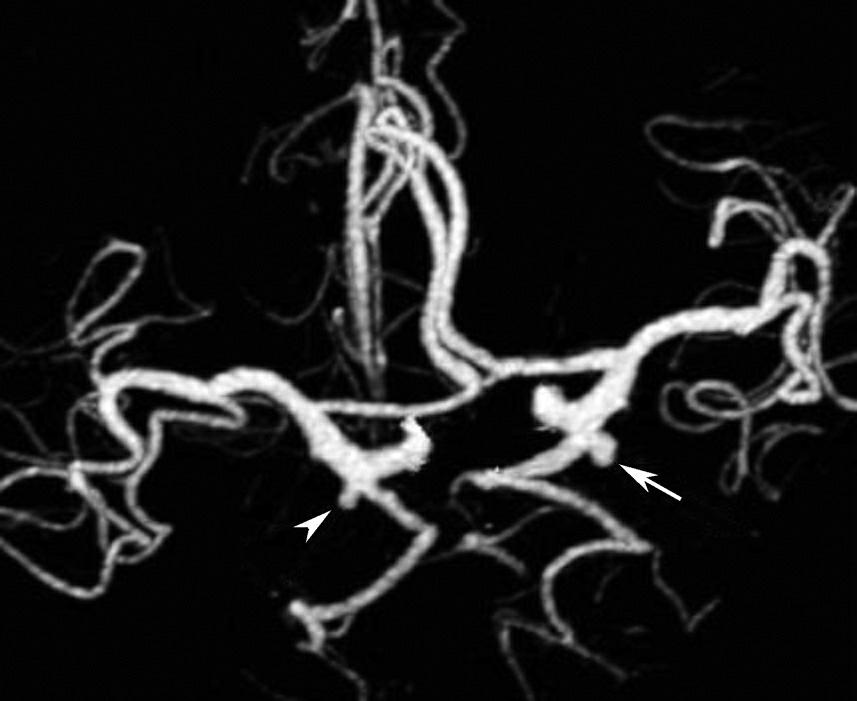

CT血管成像(CT angiography,CTA及CT venography,CTV)通过三维重建技术可显示颅内动静脉的走行、血管壁及血管周围等情况(图1-2-73~图1-2-75)。

图1-2-73 正常颅脑CTA

1.大脑前动脉;2.大脑中动脉;3.颈内动脉;4.大脑后动脉;5.基底动脉;6.椎动脉

图1-2-74 正常椎基底动脉CTA

1.基底动脉;2.颈内动脉;3.颈总动脉;4.颈外动脉;5.椎动脉

图1-2-75 正常颅脑CTV

A.侧位;B.侧位标注

1.上矢状窦;2.直窦;3.乙状窦;4.窦汇;5.大脑大静脉

基底动脉开窗畸形的发生机制被认为是胚胎第5周时成对的胚胎性神经动脉融合障碍,或为原始侧动脉残留所致(图1-2-78)。

图1-2-78 基底动脉开窗畸形(箭)

永存三叉动脉是颈内动脉海绵窦段与基底动脉之间的胚胎性吻合,为颈内动脉系统与椎基底动脉系统之间最常见的异常交通,是根据它伴行的颅神经而命名的。其他异常吻合包括永存听动脉、永存舌下动脉及永存寰前节间动脉(图1-2-79)。

图1-2-79 永存三叉动脉

A、B.异常吻合支沟通至右侧海绵窦(箭);基底动脉(长箭)